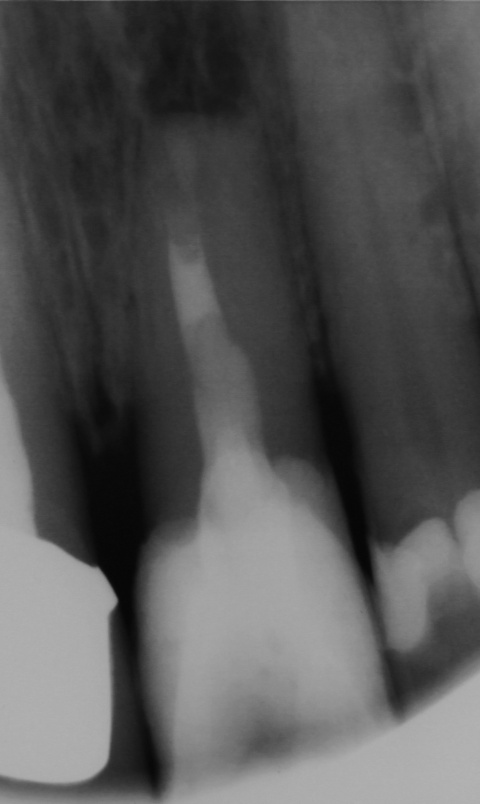

OP, es zeigt sich eine annähernd vollständige

Ausheilung der Resektionshöhle.

Zahn 22, zudem zeigen sich Kalzifizierungen im

Bereich des Wurzelkanaleinganges.

Eine 39-jährige Soldatin stellte sich im Januar 2020 mit Druckbeschwerden Regio 22 in unserer Abteilung vor. Wie auch in der vorangegangenen Falldarstellung konnten die Beschwerden mit Druck auf das Vestibulum verstärkt werden. Der Perkussionstest fiel deutlich positiv, der Vitalitätstest hingegen negativ aus. Eine erhöhte Lockerung des Zahnes lag, trotz des eindrucksvollen Röntgenbefundes, nicht vor. Erste Beschwerden traten laut Aussage der Patientin bereits 2014 auf. Das zu diesem Zeitpunkt angefertigte Röntgenbild zeigte keinen signifikanten pathologischen Befund, woraufhin die Situation weiterhin beobachtet wurde. Das aktuell angefertigte Röntgenbild zeigte eine umfangreiche periapikale Osteolyse, welche sich bis zu den Wurzelspitzen 21 und 23 erstreckte. Der Vitalitätstest der beiden benachbarten Zähne fiel positiv aus.